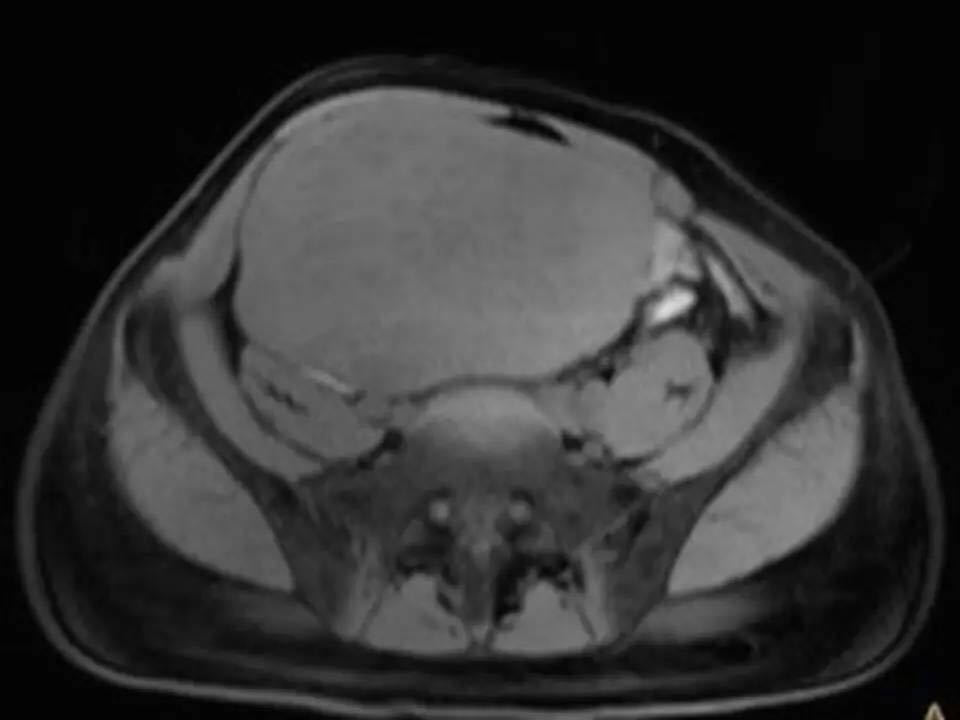

MRI表现,腹盆腔见不均质肿块,与肌肉相比为等低密度,强化不明显。T1WI信号均匀,T2WI高低混杂信号,增强后渐进性强化,病变各序列可见斑片状低信号区。 诊断,腹腔侵袭性纤维瘤病。

AF的影像学表现具有一定特征性。影像上表现为边界欠清的软组织肿块,钙化、出血少见,即便在较大的肿瘤中也看不到中央性坏死。病灶CT密度欠均匀,与邻近骨骼肌相近,强化不明显。T1WI信号基本均匀,明显或中度强化,典型强化方式呈渐进性。所有序列中都可以看到一定的低信号区,在病理上相对应的为病变内胶原纤维丰富的区域,此区域强化较轻。 侵袭性纤维瘤病虽然少见,但是平常工作中需要考虑到侵袭性纤维瘤病的诊断,尤其是中年女性腹腔的肿块。MRI为最佳的检查方法,可以显示一定的影像学特征。